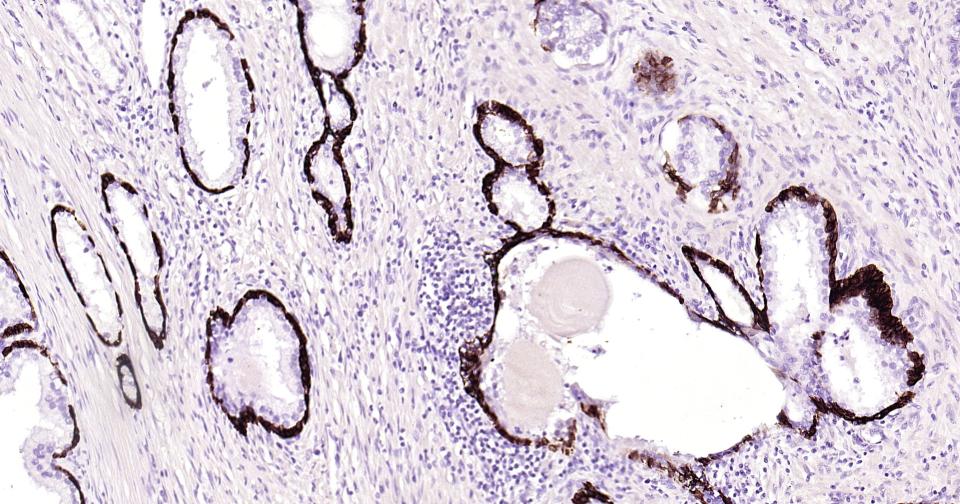

Paraformaldehyde-fixed, paraffin embedded Human Prostate; Antigen retrieval by boiling in sodium citrate buffer (pH6.0) for 15 min; Antibody incubation with Cytokeratin 14? Monoclonal Antibody, Unconjugated(bsm-52054R) at 1:200 overnight at 4°C, followed by conjugation to the bs-0295G-HRP and DAB (C-0010) staining.